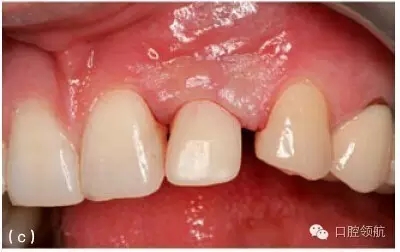

另外一個方面,深的袖口將妨礙修復體完全就位(圖9.26)。通??梢酝ㄟ^放射學檢查,確認修復部件的就位情況,包括種植體與基臺的連接部分。即使是內(nèi)連接,轉(zhuǎn)移體或者其他修復部件也會因深袖口而不能就位。以下技術可以用于解決這些問題:可以在局部麻醉下,插入喇叭狀或者外展的基臺,以非手術的方式擴大袖口(圖9.27 a,b),然后再通過放射學檢查確定部件的完全就位。組織會受壓發(fā)白,15分鐘后,軟組織將會擴張,以允許理想修復部件的就位,這樣治療將得以繼續(xù)。有時,需要在鄰面做兩個小切口,以緩解袖口軟組織張力(圖9.28 a,b)。通常不需要縫合。一旦袖口組織塑形完成,可運用最佳塑形的臨時(圖9.29)或最終部件(圖9.30),來維持理想的軟組織外形。

圖9.30 (a)最終基臺及修復體,用于塑造或者保存已成形的牙齦袖口。(b)口內(nèi)觀,下頜切牙區(qū)域,種植體周良好的三角形牙齦袖口。